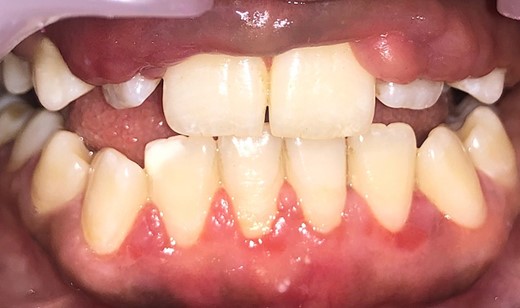

On the day of the procedure, a complete blood test was done which shows normal limit values. Following the administration of local anesthesia, periodontal pockets were checked (Fig. 2) and the bleeding points were marked using a Krane Kaplan pocket marker, (Fig. 3) continuous incision was made with the scalpel and blade no. 15, keeping the bevel at ~45° to the tooth surface. Once the incisions had been made, the excision of the tissue was done with a curette (Fig. 4). Further electrocautery was used as a coagulating machine to control the bleeding. Gingivoplasty, i.e. reshaping and recontouring of gingiva following the normal festooned pattern was done. Coe-Pak was placed and the patient was recalled after 1 week for check-up (Fig. 5).

Measuring the periodontal pocket of lower anteriors showing gingival enlargement.